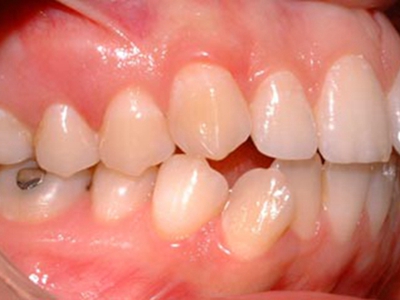

阻生牙是指由于邻牙、骨或软组织的阻碍而只能部分萌出或完全不能萌出,且以后也不能萌出的牙。引起牙阻生的成因,主要是由于颌骨缺乏足够的空间容纳全部恒牙。常见的阻生牙为下颌第三磨牙、上颌第三磨牙及上颌尖牙。

发育正常的牙齿同时正畸治疗又不需要进行拔牙矫治,通常需要对阻生牙进行牵引治疗,引导进入牙弓,而对于发育异常的阻生牙加之正畸治疗需要进行拔牙矫治,通常可以考虑将阻生牙拔除,而避免再拔发育正常的前磨牙,即降低了正畸治疗的难度及不确定性,又保留了相对正常的牙齿。